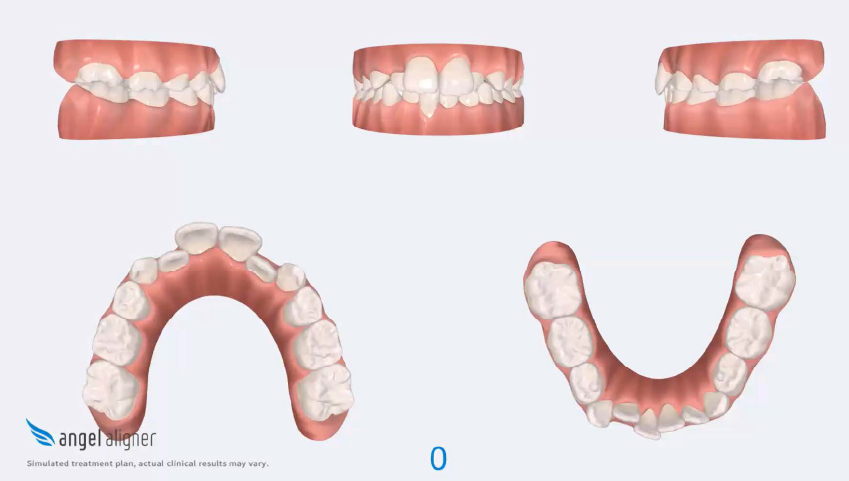

The orthodontic treatment plan was designed to address dentoalveolar crowding, transverse discrepancies, and midline deviations, while maintaining optimal periodontal health and achieving stable Class I molar and canine relationships. Specific objectives included correction of anterior crossbite, expansion and coordination of the arches, derotation of upper molars, preservation of incisor inclinations, derotation of lower posterior teeth with lingual root torque, leveling of the curve of Spee through incisor intrusion and controlled extrusion of deciduous teeth, and normalization of incisor inclinations. A clear aligner–based approach was selected to allow precise, controlled tooth movement, with particular

attention to root parallelism in the anterior region. The treatment was carried out in two phases: an initial phase of 20 aligners focused on primary alignment, space redistribution, and preliminary correction of malocclusion, followed by a refinement phase of 10 aligners aimed at finalizing tooth positioning, improving intercuspation, optimizing overbite and overjet, and enhancing overall occlusal stability. The refinement phase was considered an integral component of the treatment strategy and is explicitly highlighted to emphasize its role in achieving optimal finishing and long-term functional and aesthetic outcomes.

To correct the anterior crossbite, occlusal pads were placed on teeth 36 and 46 to provide localized bite opening and facilitate proper anterior guidance. Optimized double semielipsoidal attachments were placed on the upper anterior teeth to ensure controlled root divergence and precise torque expression. Posterior teeth received lingual root torque to maintain proper axial inclinations, while interproximal reduction (IPR) was performed on deciduous teeth to create space as needed, carefully avoiding any proclination of the lower incisors.